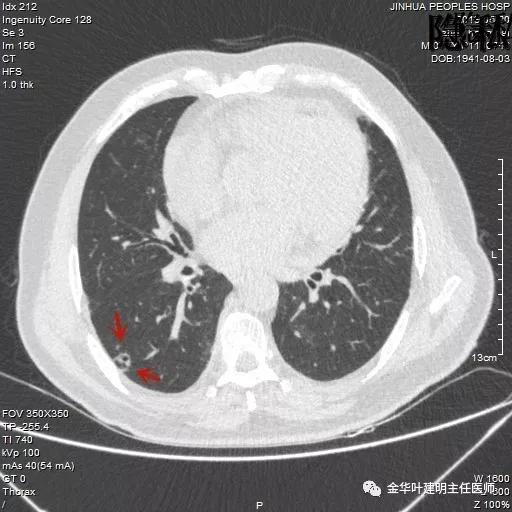

金华的周某,今年已经78岁了,上个月底单位退休人员体检,查出他的右肺有一结节,结果出来后,这个月通知他到胸外科复诊。因为是我的亲戚,便直接找到了我,我从电脑里调出他的CT片,如下所示:

可见其右下叶有一空腔性病灶,壁薄,病灶下方见到实性密度的成份。我们看过目前的片子后,马上想到的是此病灶以前有没有,对比是非常重要的。调出之前片子: